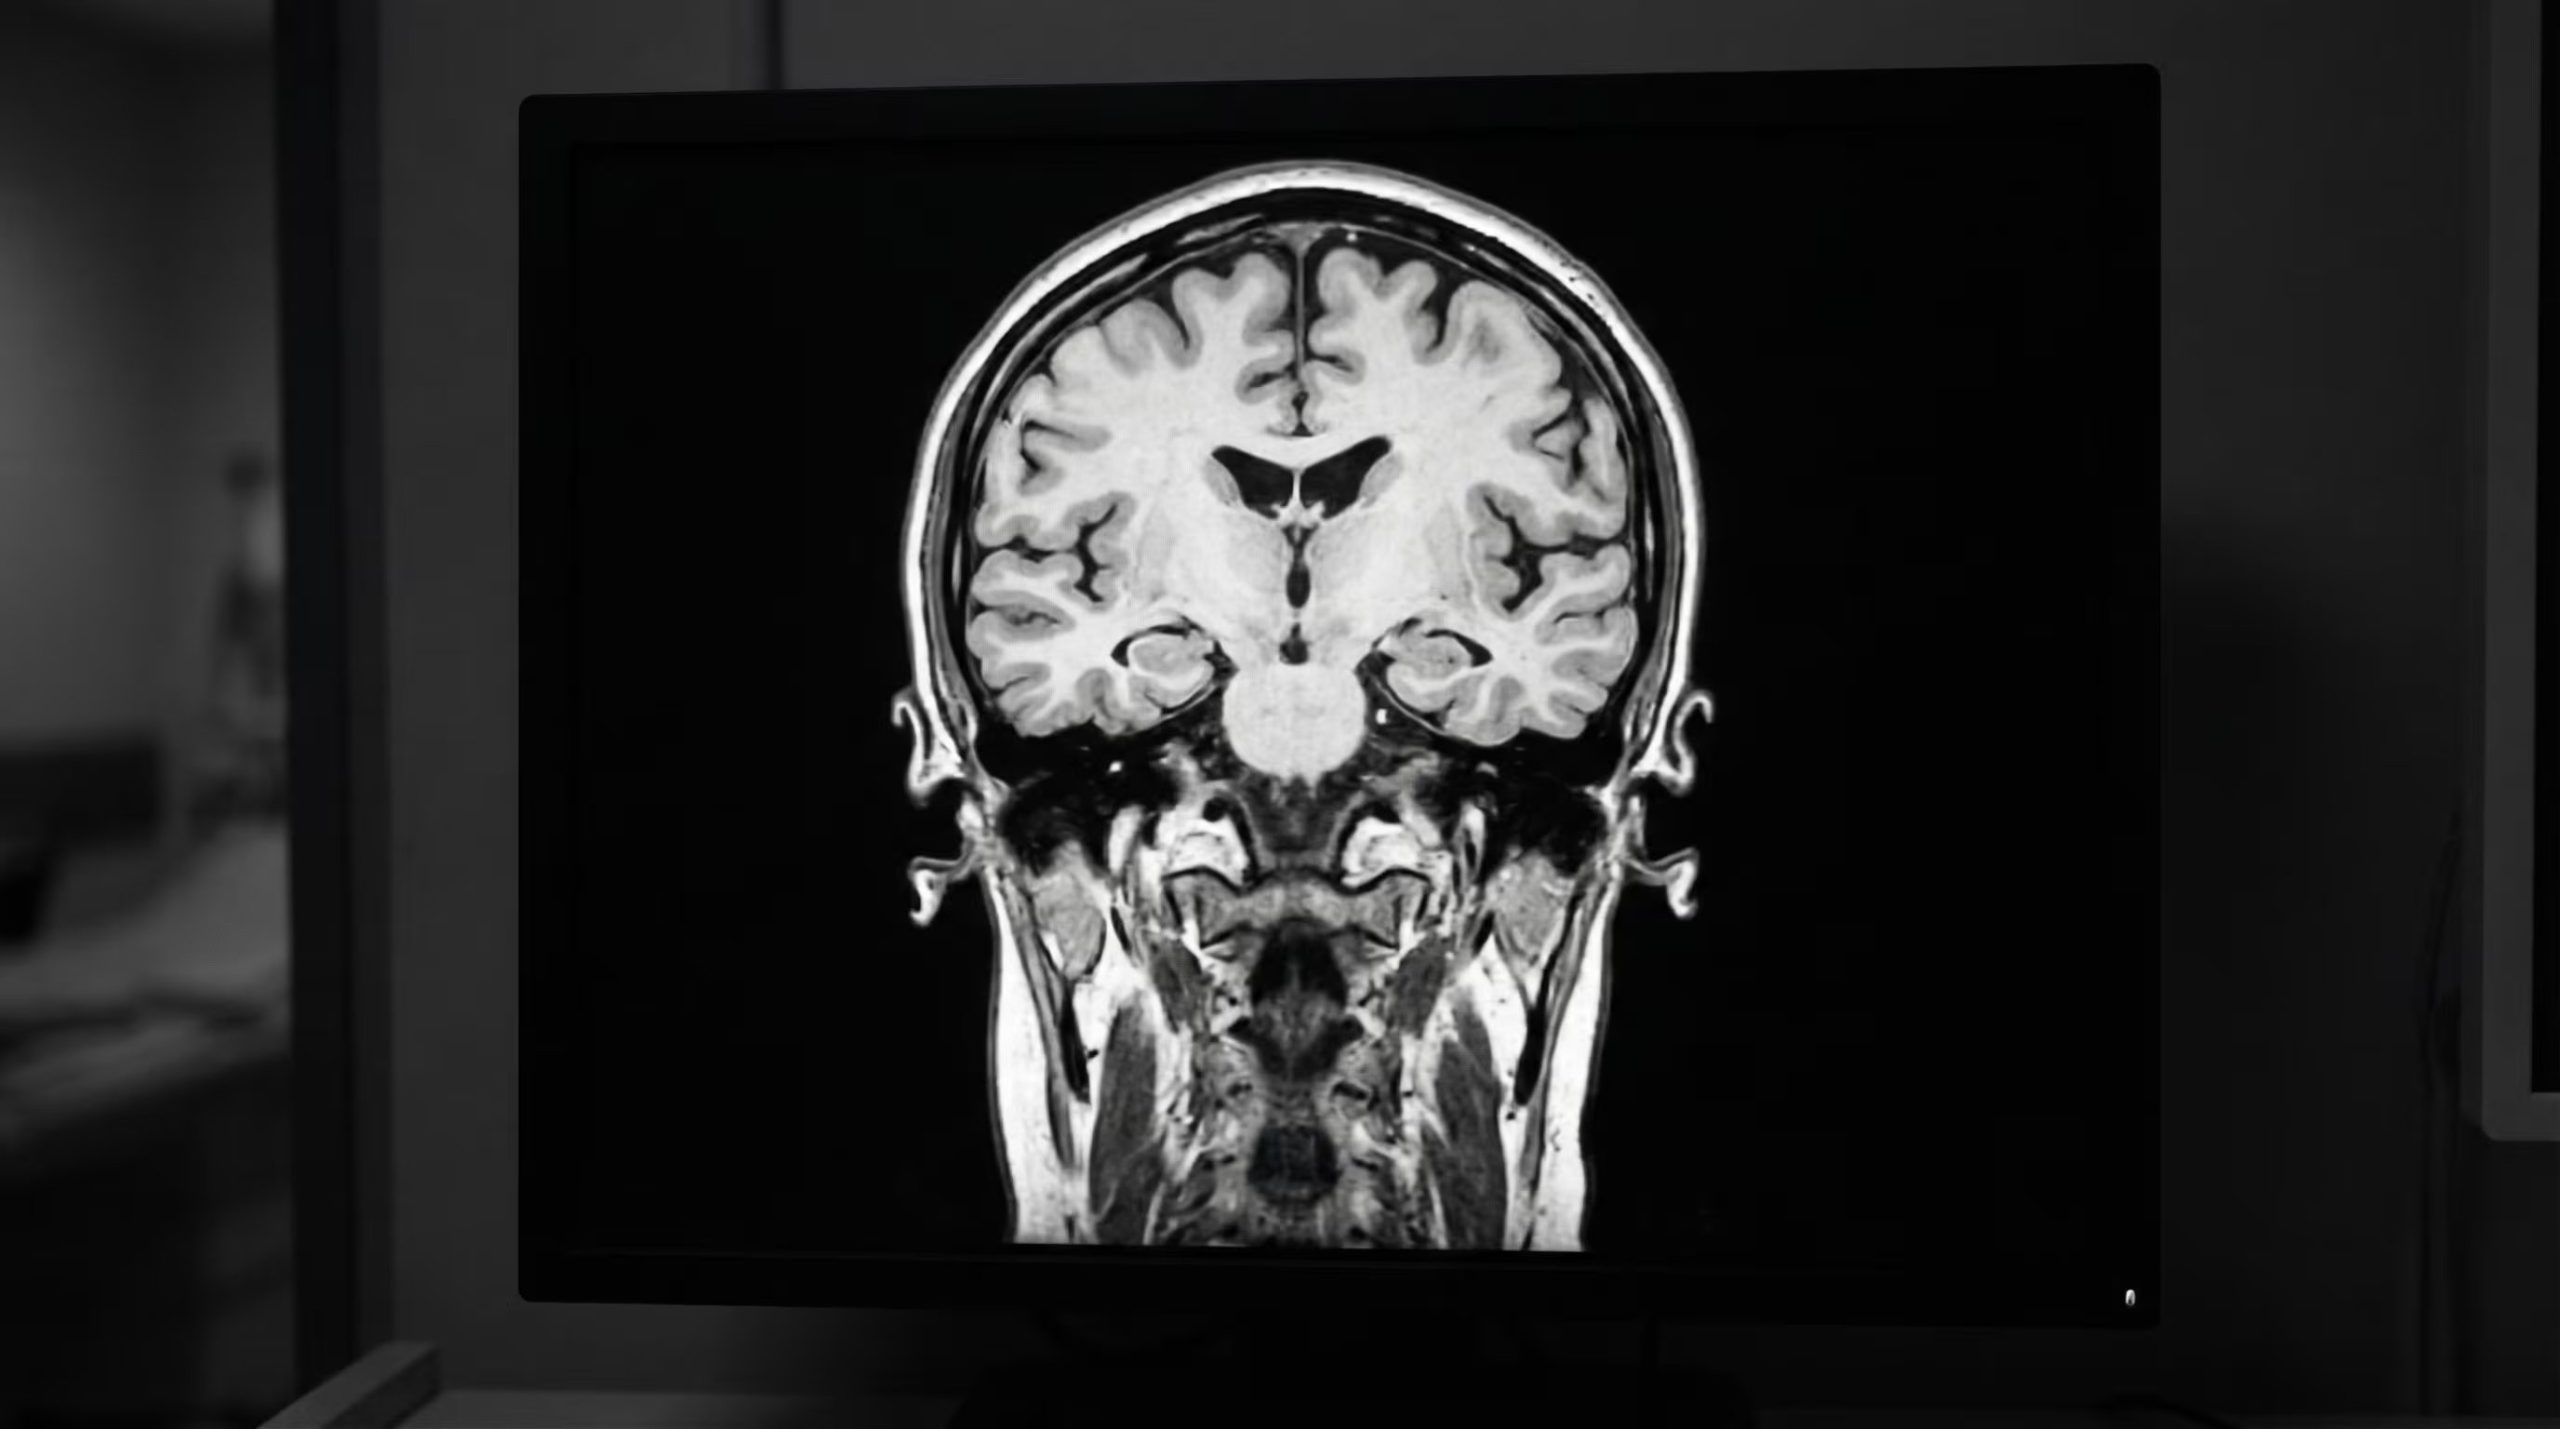

Lograr identificar el punto de partida de las enfermedades neurodegenerativas durante la niñez representa uno de los desafíos más complejos para la ciencia médica actual. En este escenario, un trabajo de investigación internacional coordinado por la Flinders University ha conseguido precisar el mecanismo elemental en el progreso de la demencia infantil vinculada al síndrome de Sanfilippo, una patología genética de baja frecuencia pero de consecuencias severas.

La investigación ha comprobado que una perturbación temprana en la transmisión de mensajes entre las neuronas —fenómeno llamado hiperactividad sináptica— podría constituir el detonante del daño cerebral.

El estudio ha determinado que la anomalía se gesta en la sinapsis, el espacio de conexión donde las células nerviosas intercambian impulsos. Este mecanismo es fundamental para procesos vitales como el aprendizaje, la memoria y la regulación de la conducta.

En los infantes que padecen este síndrome, el equipo de investigación detectó una actividad desmedida en estos circuitos. En lugar de operar bajo un esquema equilibrado, las neuronas presentan una hiperactividad que distorsiona las funciones cerebrales desde fases muy precoces.